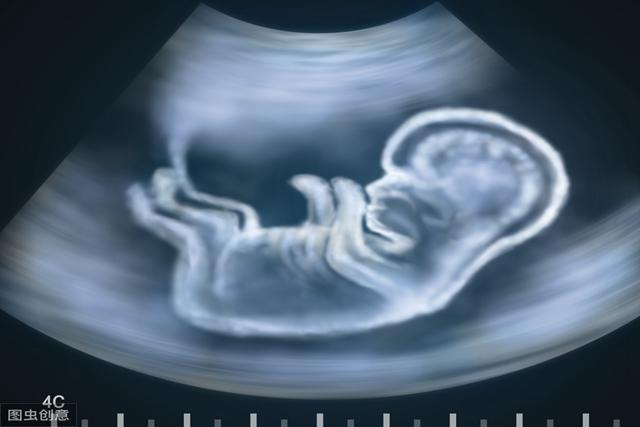

在妈妈子宫内待满40周的宝宝,出生就“赢在起跑线上”,别羡慕

其实当妈的心都是可以理解的,不过孕妈们都忽略了一个问题,你知道吗?胎宝宝在妈妈子宫里待满40周,很多方面会让人很羡慕呢,尤其是这些方面,出生就“赢在起跑线上”,别羡慕!来看下是哪些方面,你知道后,说不定就不会老想着要让宝宝早点生出来了。